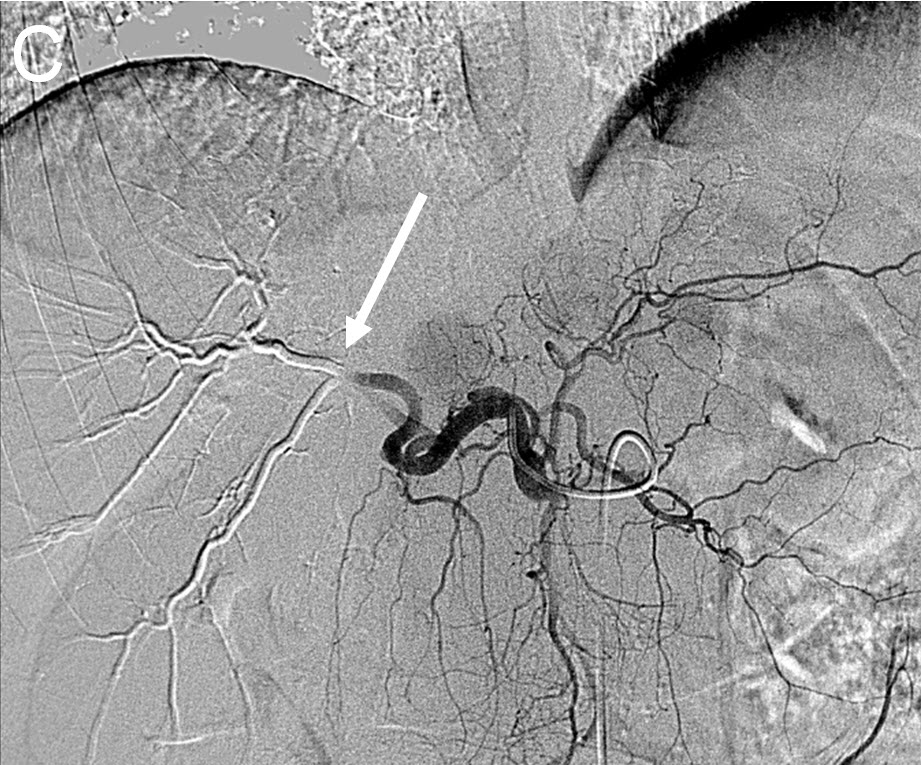

Treating Multiple Liver Tumors with Drug Eluting Beads (DEB TACE)

|

| (C) Angiogram after right hepatic artery(white arrow) embolization using Drug Eluting Beads (DEB TACE) |